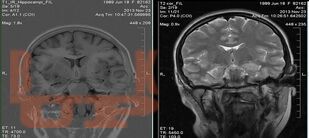

В учебном пособии освещены современные подходы к патогенезу височной эпилепсии, связанные с процессами нейровоспаления и нейродегенерации. Отражена углубленная информация о клинико-диагностических маркерах заболевания, в том числе, касающаяся изучения биохимических и генетических биомаркеров височной эпилепсии.